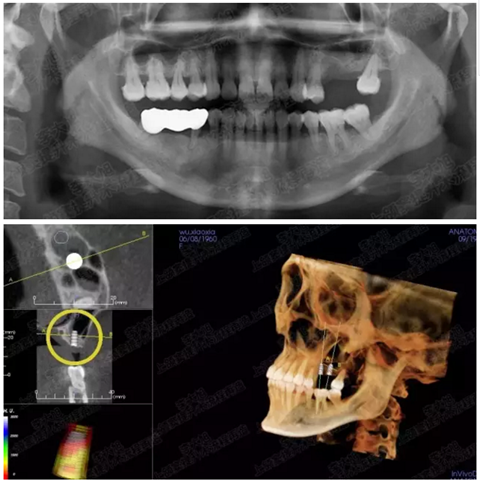

病例二

剩余骨量2mm

003.png

提升10mm

004.png

病例三

剩余骨量3mm

005.png

006.png